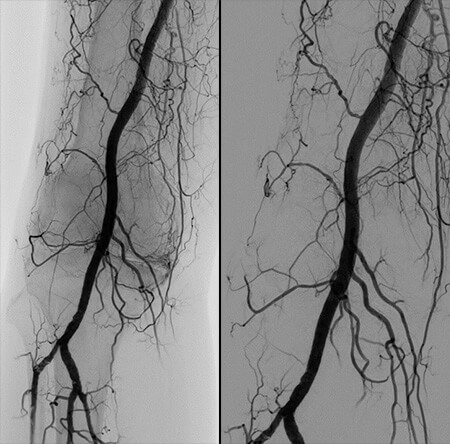

GAE is a novel procedure to close off abnormal blood vessels in the knee and help alleviate pain associated with knee OA. It is performed by Interventional Radiologists with specific expertise in using real-time imaging guidance to navigate a small catheter to the knee joint and deliver microscopic beads that block arteries. The procedure is performed through a pinhole incision at the groin with the use of x-ray dye. By blocking blood flow to the knee, inflammation associated with osteoarthritis is decreased and pain is reduced. Studies have shown significant improvements in pain in 60 percent to 80 percent of patients, as well as a significant decrease in pain medication use. Although pain relief typical extends for 6-12 months, a few studies have documented benefit beyond 2 years.